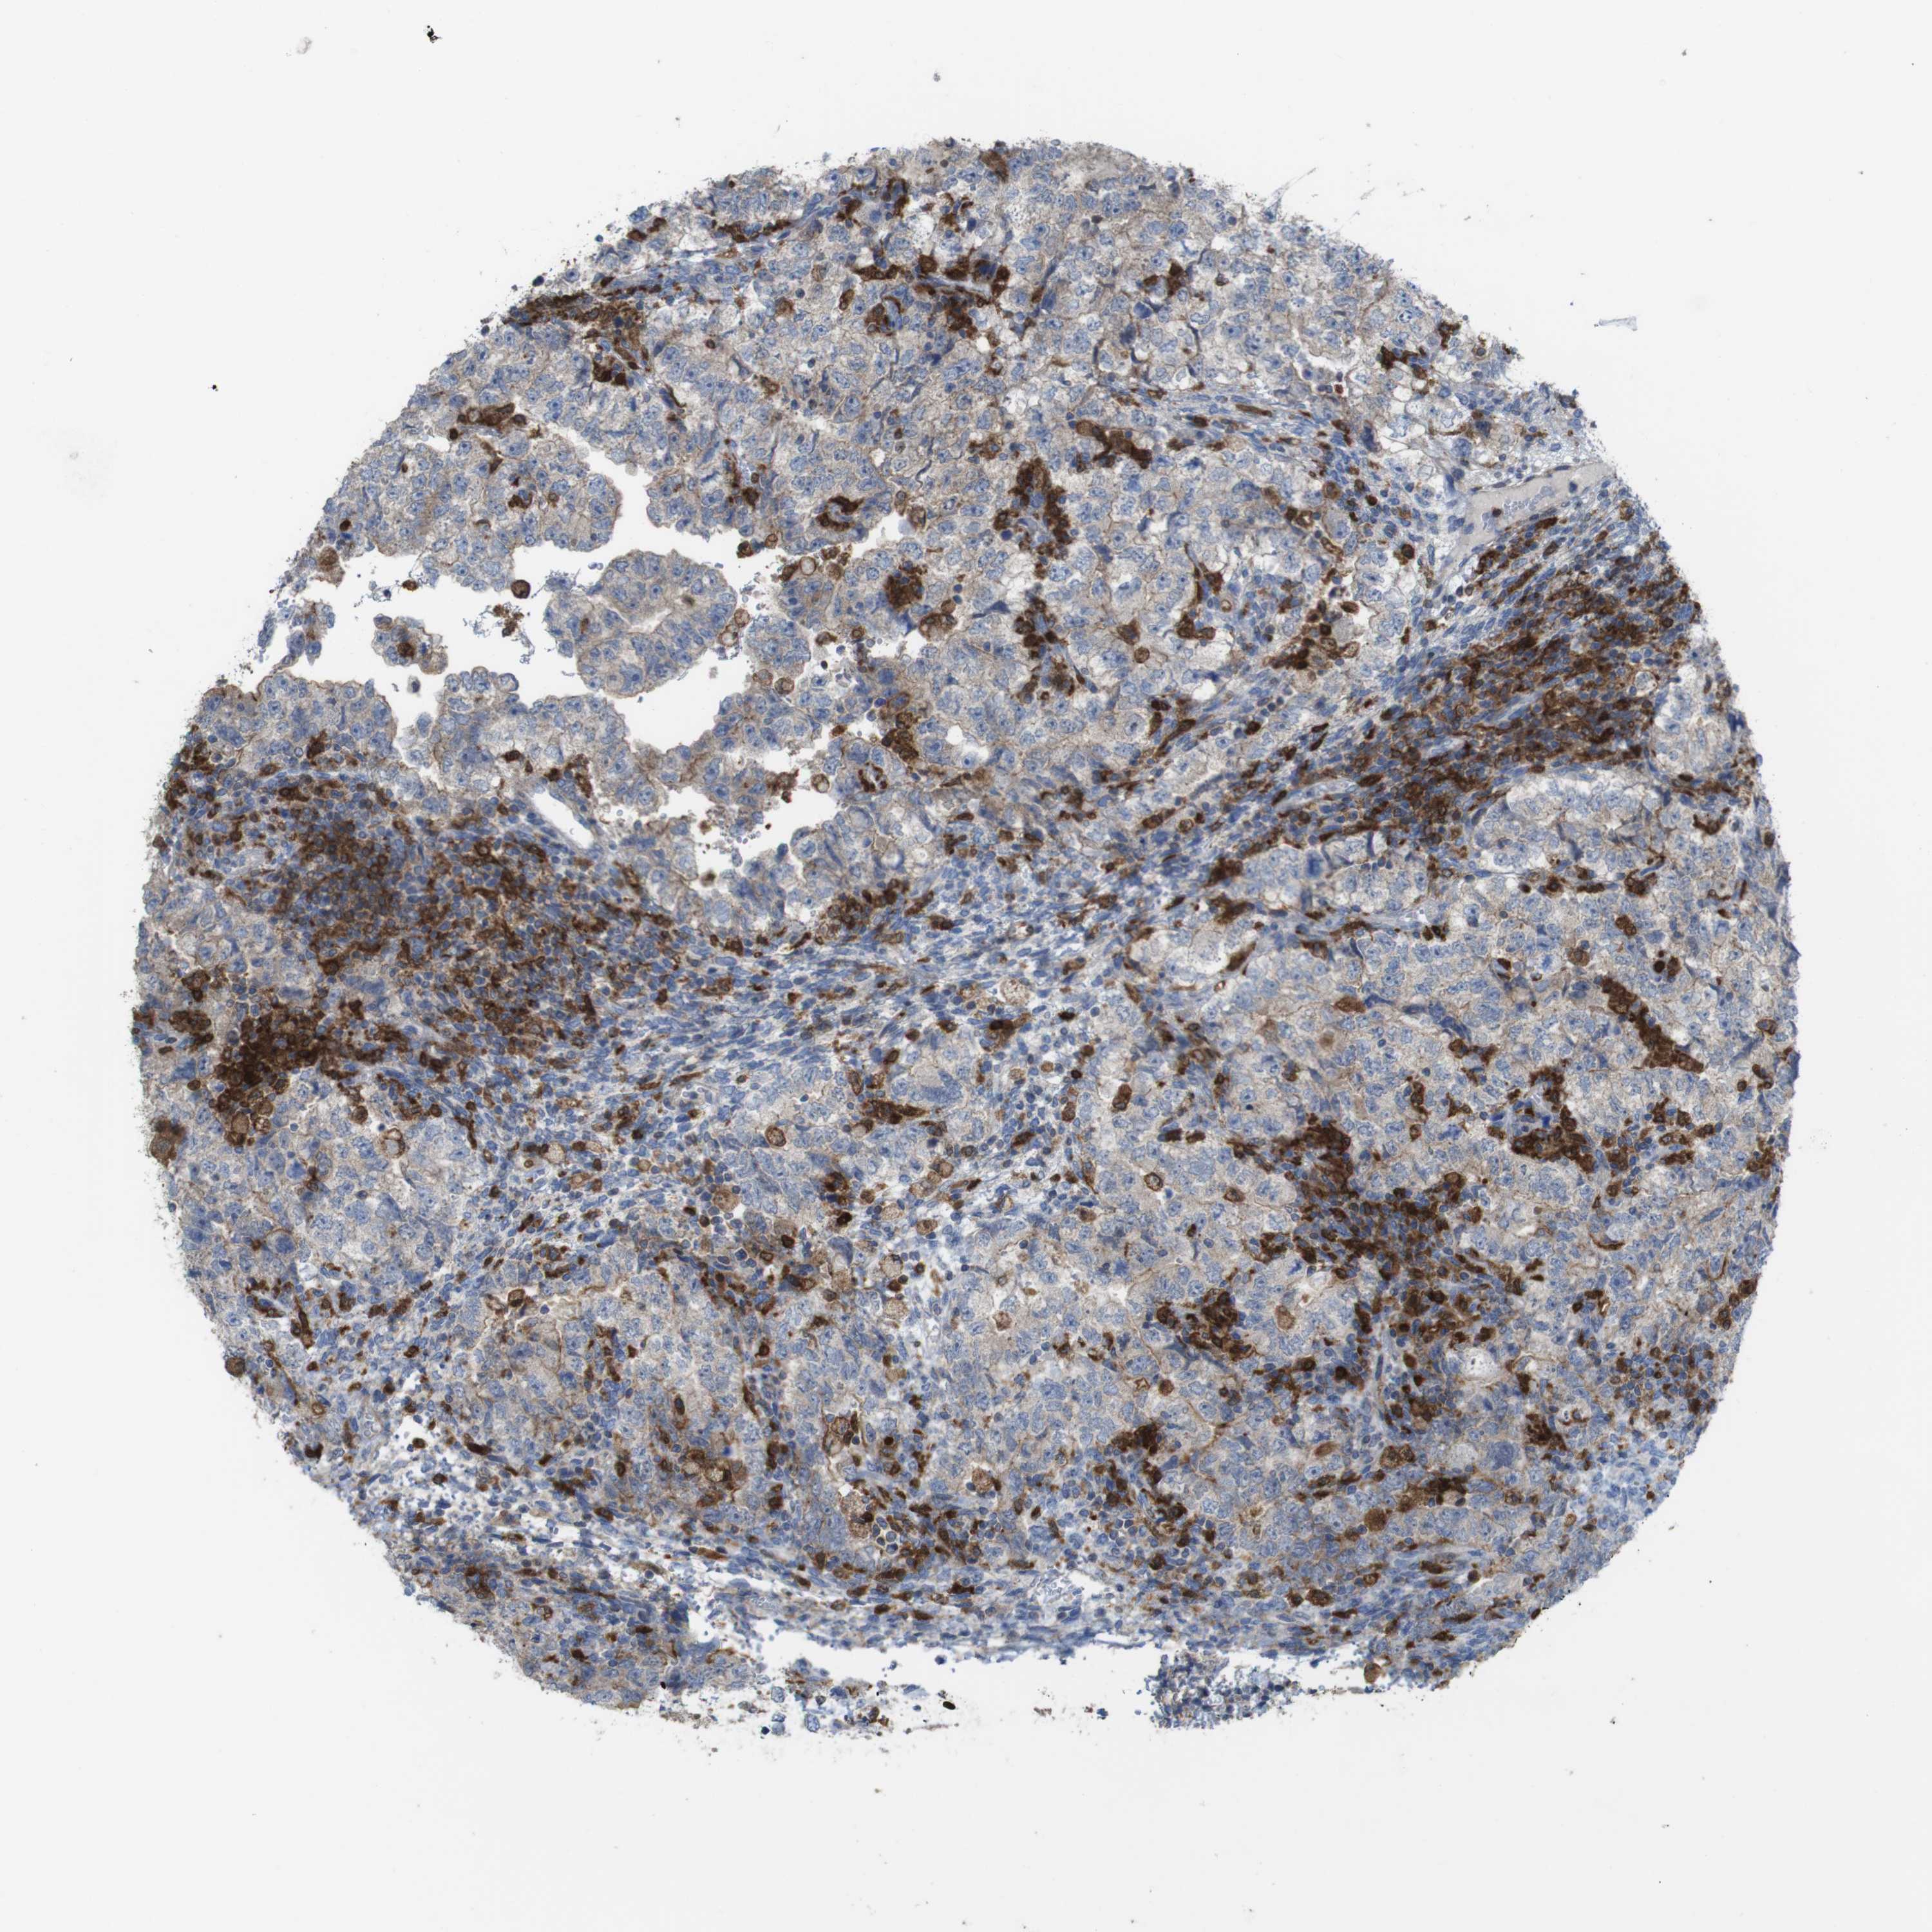

TESTIS CANCER - Protein expressioni

A mouse-over function shows sample information and annotation data. Click on an image to view it in a full screen mode. Samples can be filtered based on level of antibody staining by selecting one or several of the following categories: high, medium, low and not detected. The assay and annotation is described here.

Note that samples used for immunohistochemistry by the Human Protein Atlas do not correspond to samples in the TCGA dataset.

Antibody stainingi

Antibody staining in the annotated cell types in the current human tissue is reported as not detected, low, medium, or high, based on conventional immunohistochemistry profiling in selected tissues. This score is based on the combination of the staining intensity and fraction of stained cells.

Each image is clickable and will lead to virtual microscopy that enables deeper exploration of all samples and also displays staining intensity scores, fraction scores and subcellular localization as well as patient and tissue information for each sample.

Antibody HPA001890

High

Medium

Low

Not detected

Intensity

Strong

Moderate

Weak

Negative

Quantity

>75%

75%-25%

<25%

None

Location

Nuclear

Cytoplasmic/membranous

Cytoplasmic/membranous,nuclear

Seminoma, NOS

Carcinoma, Embryonal, NOS